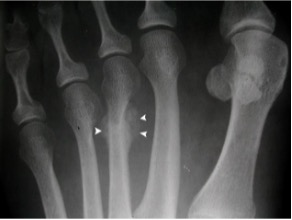

Second (and third) metatarsal

- 2nd and 3rd rays are stiffer therefore sustain ~90% of metatarsal stress fractures

- 75% at head / neck junction; usually heal well

- Proximal fractures seen in ballet dancers or those with TNJ fusions; more prone to non-union

- Often difficult to see on initial X rays but apparent later